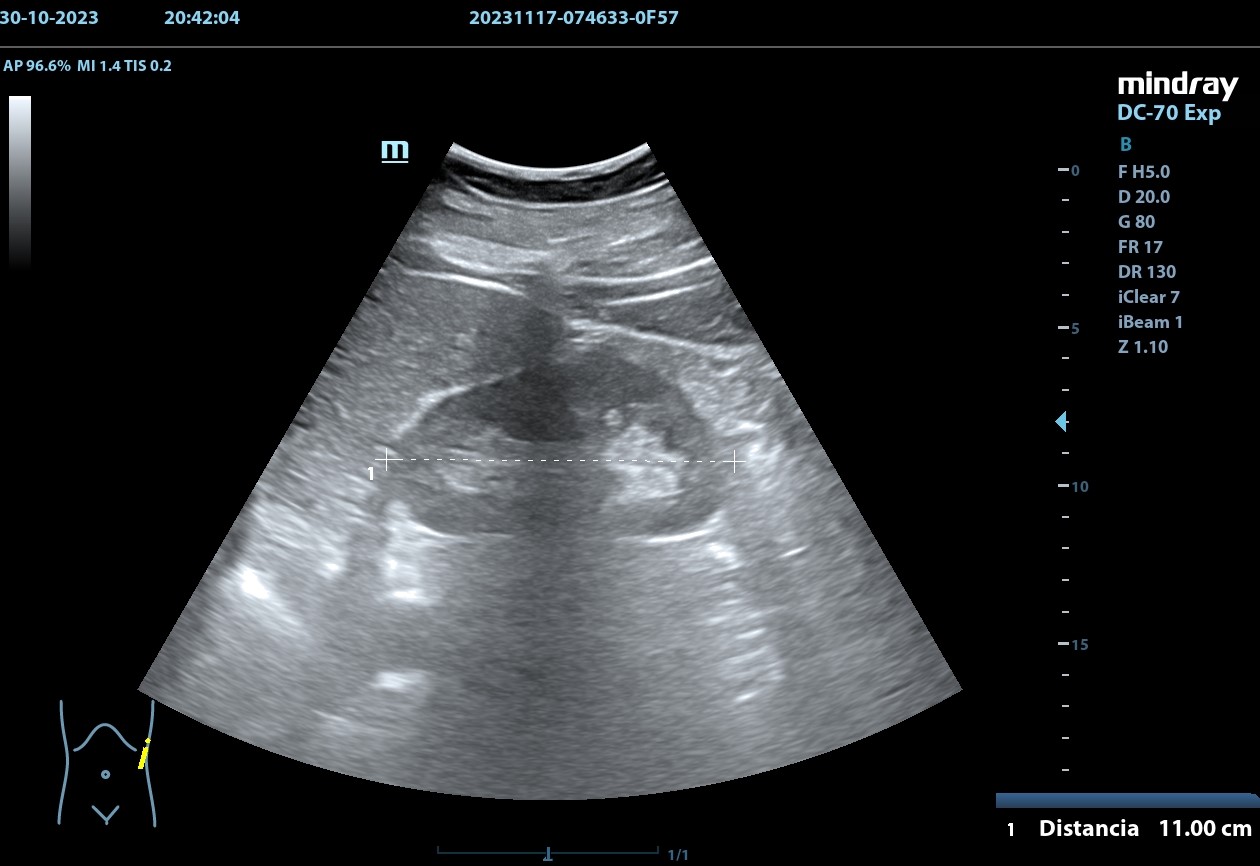

Se realiza, en consulta, una ecografía de las vías urinarias (POCUS), apreciando una lesión excrecente, pediculada, de 7,48 x 6,14 cm, que afecta a la pared izquierda y superior de la vejiga. Doppler negativo. No apreciándose jets ureterales. Riñón izquierdo de 11cm, y derecho de 9.27 cm, sin signos de dilatación de las pelvis renales que sugieran hidronefrosis.